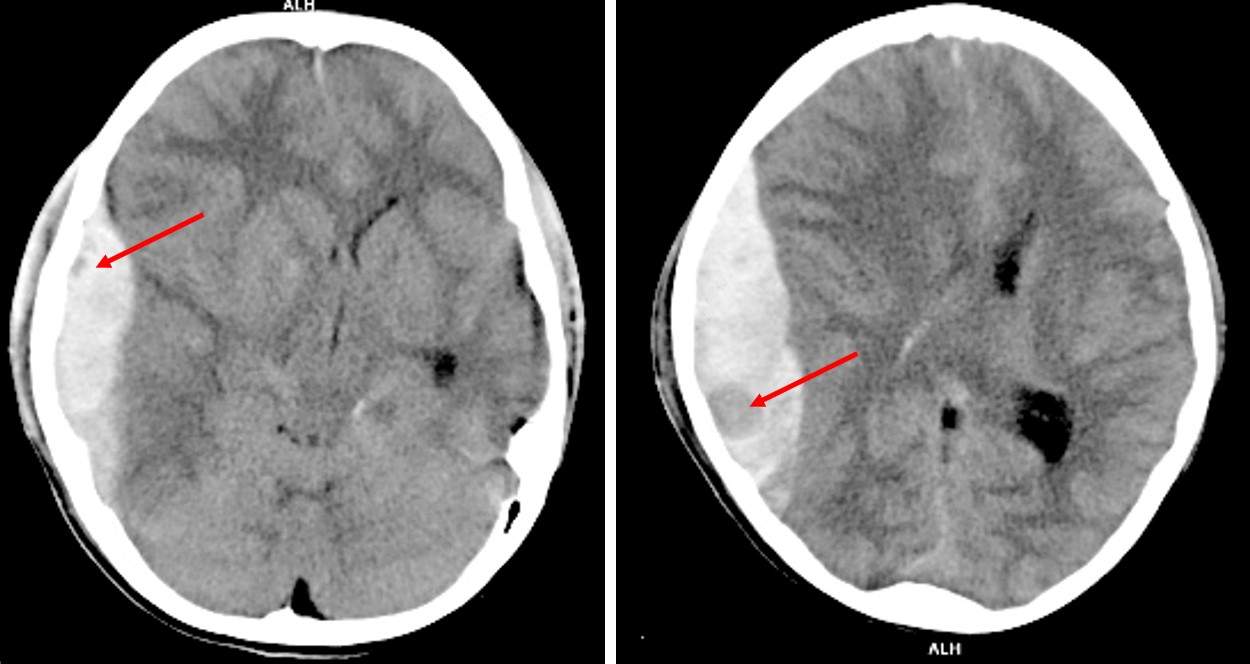

30 Years Old Man Involved in Motor Vehicle Accident Post category:Spot Diagnosis Post published:July 13, 2023 Share on Facebook Share on X (Twitter) Share on Pinterest Share on Email Share on Reddit Non-contrast CT brain axial plane in soft tissue window A 30 years old man involved in motor vehicle accident presented with headache and persistent vomiting. GCS on arrival in emergency department was 14/15. What’s the diagnosis ? FULL CASE AND ANSWER Share on Facebook Share on X (Twitter) Share on Pinterest Share on Email Share on Reddit Read more articles Previous PostGeneralized Pustular Eruptions Next PostPainful Hand Ulcerations and Shortness of Breath You Might Also Like Patient with Decreased Appetite, Vomiting, Weight Loss and a Mass Through the Umbilicus November 29, 2021 A Diagonal Crease in Each Earlobe September 7, 2021 A 3-year-old Boy with Fever, Vomiting and Skin Lesions August 10, 2022